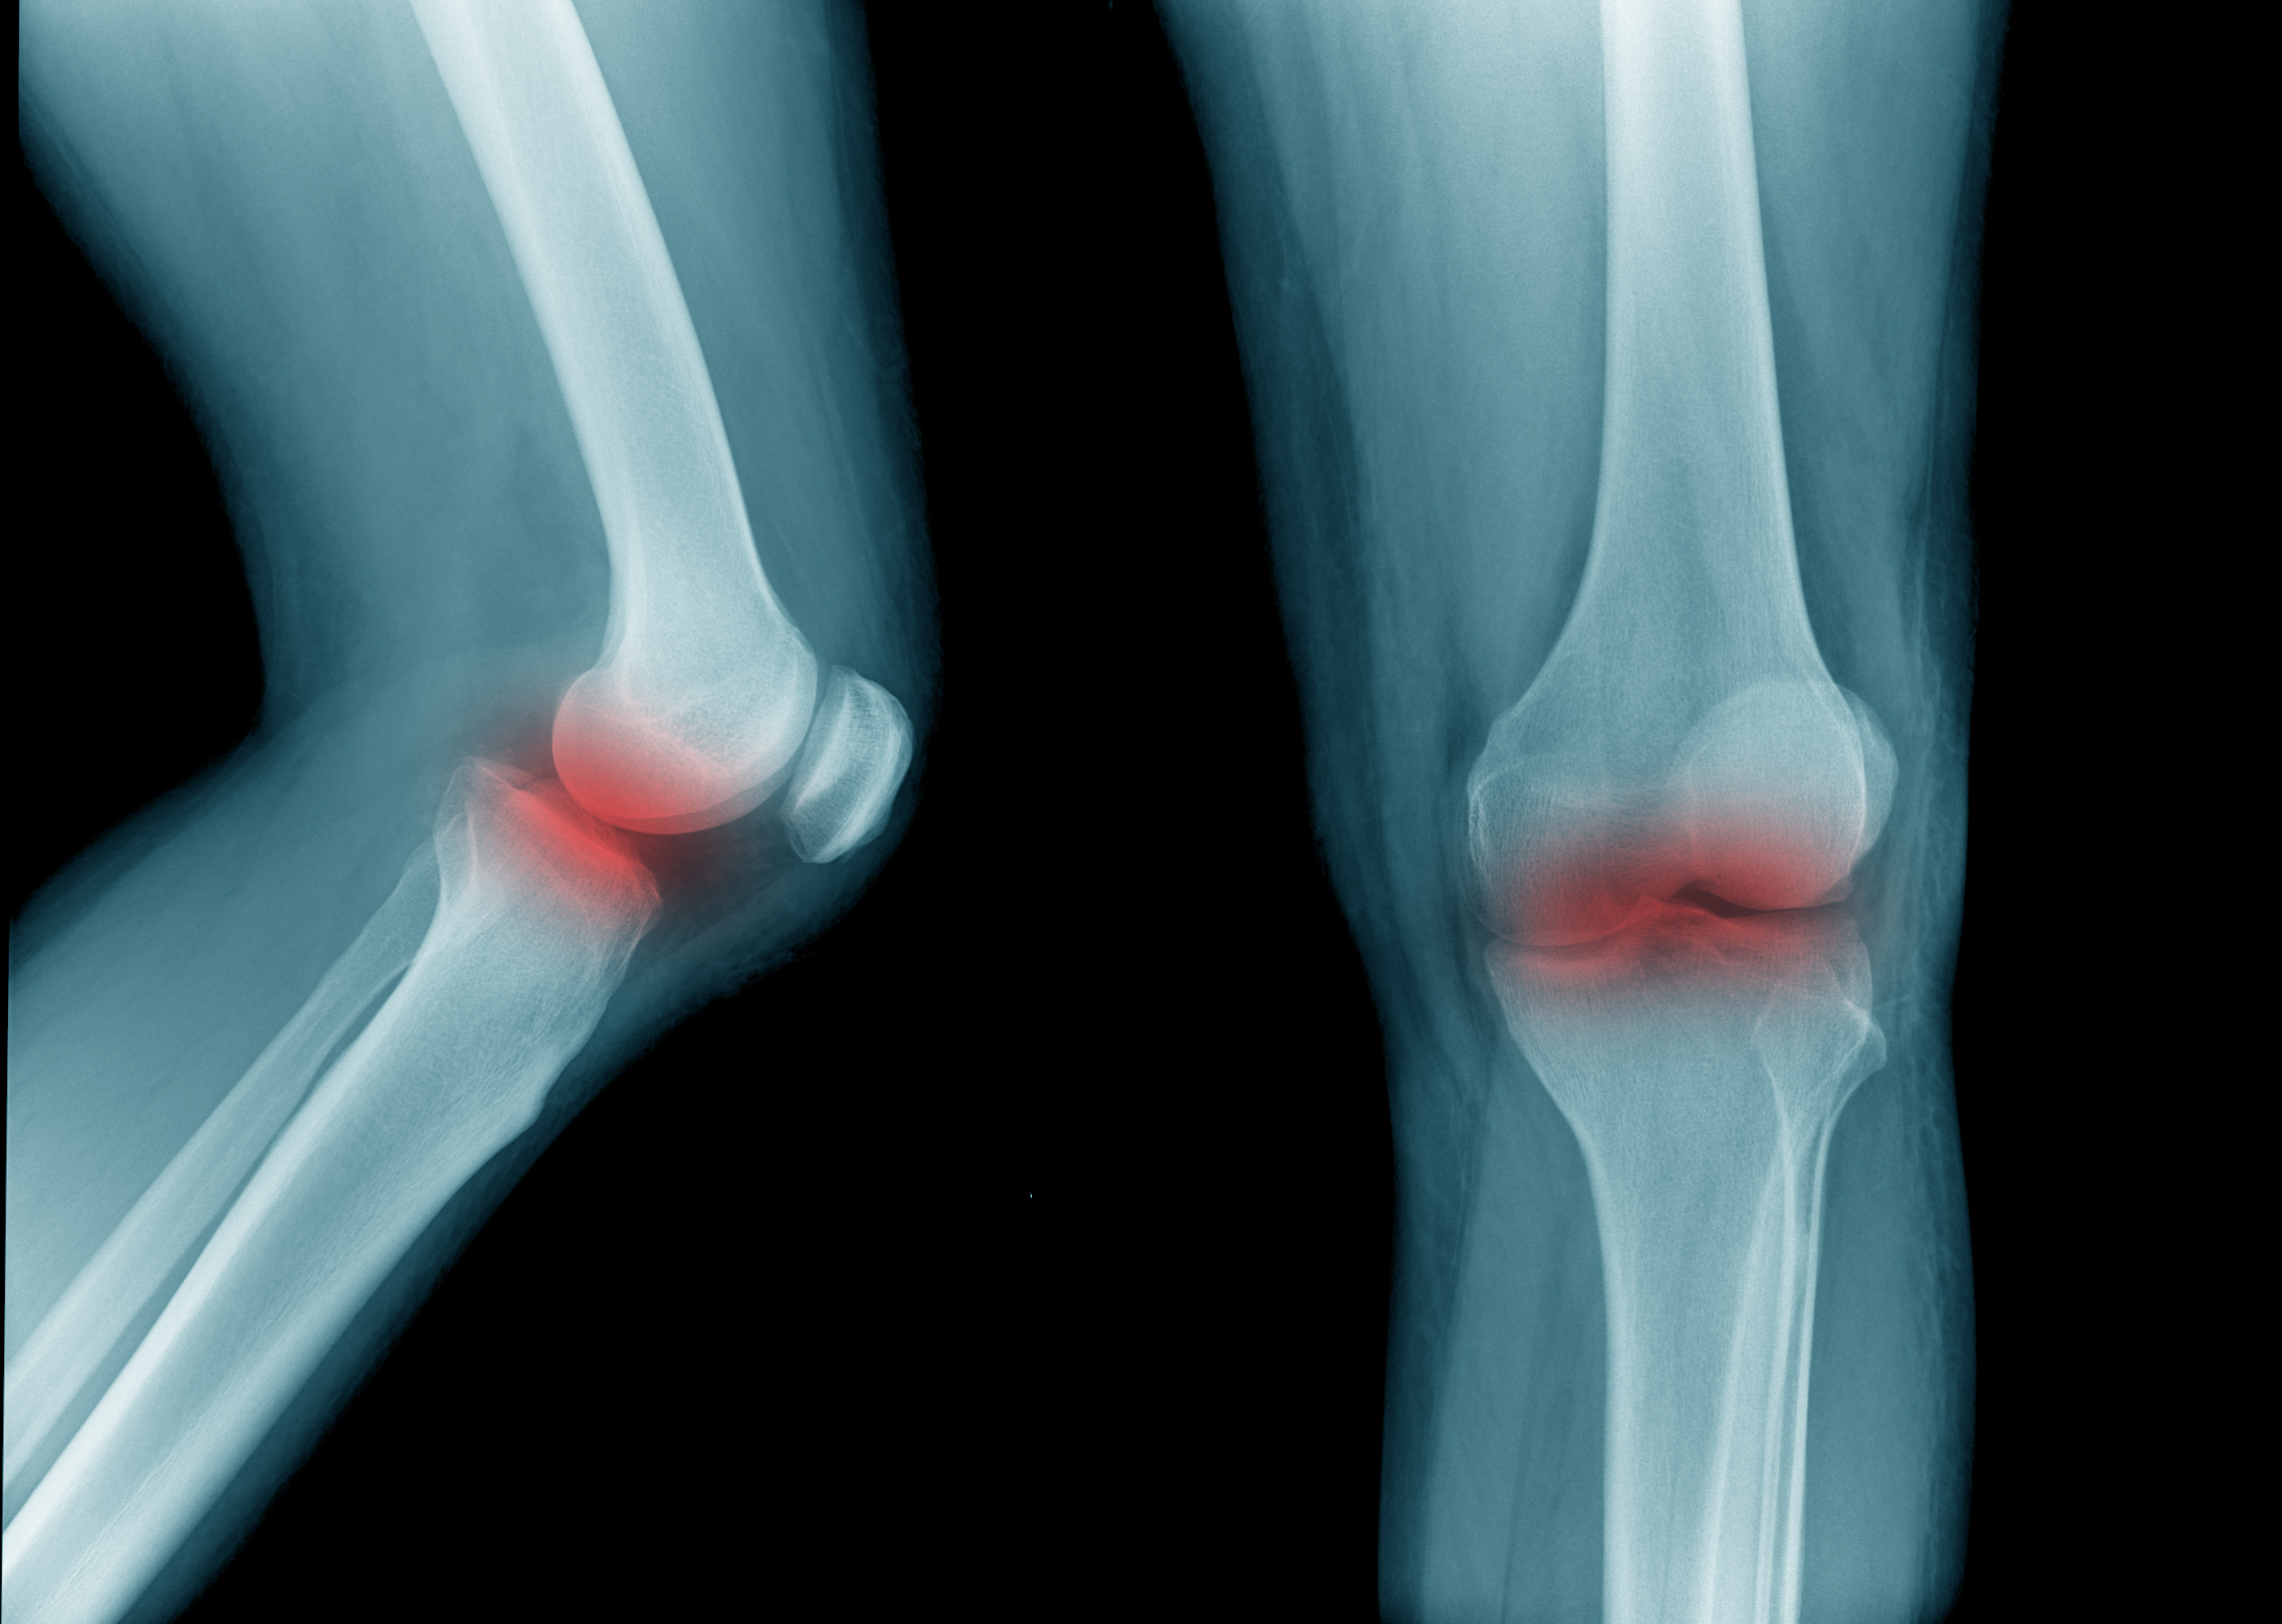

5.“My god damned knees. I used to run 10-14 miles outside every day. Now, I can barely do three miles on a treadmill before my right knee wants to give out.”